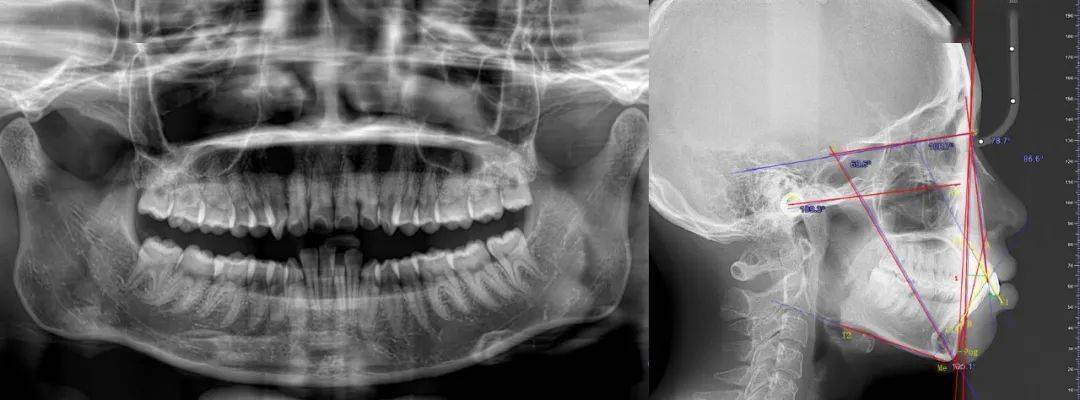

牙齿正畸头颅侧位片是口腔正畸诊疗中核心的影像学检查手段,通过拍摄头颅矢状位的X线影像,全面呈现颅面骨骼、牙齿排列及软组织形态的立体关系,为正畸诊断、方案设计及疗效预测提供客观依据,它与口内曲面断层片、全景片等共同构成正畸影像检查体系,但因能同步评估骨骼、牙齿、软组织的矢状向和垂直向结构,被誉为“正畸诊断的基石”。

- 骨骼关系评估:明确上下颌骨相对于颅骨的位置(如上颌前突/后缩、下颌前突/后缩)、面部垂直生长型(高角面型、低角面型或均角面型),判断骨性错颌的类型与程度。

- 牙齿位置分析:测量牙齿倾斜度(如上前牙唇倾/舌倾)、覆盖覆合关系(深覆盖、深覆合、反颌、开颌)、牙根与牙槽骨的相对位置,评估牙齿拥挤或间隙的原因。

- 软组织形态观察:评估唇部突度、鼻唇角、颏部形态等,预测矫治后软组织侧貌改善效果,尤其是对美学要求高的患者至关重要。

关键解读指标与临床意义

头颅侧位片的解读依赖角度、距离等客观测量指标,以下为核心参数及其临床意义:

| 指标名称 | 定义 | 正常值范围 | 临床意义 |

|---|---|---|---|

| SNA角 | 蝶鞍中心-鼻根点-上齿槽座点角 | 82°±4° | 反映上颌骨相对颅骨位置,>84°提示上颌前突 |

| SNB角 | 蝶鞍中心-鼻根点-下齿槽座点角 | 80°±4° | 反映下颌骨相对颅骨位置,<76°提示下颌后缩 |

| ANB角 | SNA角与SNB角差值(SNA-SNB) | 2°±2° | 上下颌骨相对关系,>4°上颌前突或下颌后缩 |

| 下颌平面角(MP-FH) | 下颌平面(下颌下缘切线)与FH平面夹角 | 32°±5° | 垂直生长型,>35°高角(易露龈笑),<28°低角 |

| 上中切牙角(UI-SN) | 上中切牙长轴与SN平面(蝶鞍-鼻根点)夹角 | 105°±6° | 上前牙倾斜度,>111°唇倾(易露龈),<99°舌倾 |

| 覆盖 | 上中切牙切缘至下中切牙唇面水平距离 | 2-4mm | 水平向错颌,>4mm深覆盖,<0mm反颌 |

| 覆合 | 上中切牙切缘覆盖下中切牙冠长的比例 | 1/3-1/2 | 垂直向错颌,>1/2深覆合,<0°开颌 |